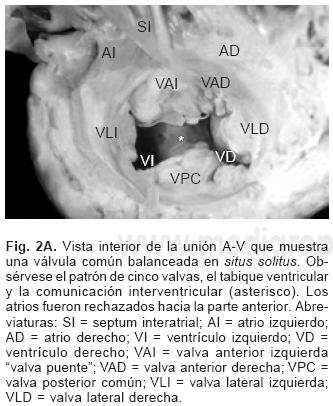

En los setenta corazones estudiados el situs atrial que predominó fue el solitus seguido de dextroisomerismo, inversus y levoisomerismo (Figs. 2A y 2B). La conexión A–V predominante fue concordante seguida de la doble entrada a ventrículo único, doble entrada a ventrículo derecho, ambigua y discordante (Tabla I). Los tipos de conexión ventriculoarterial se consignan en la Tabla II.

Sesenta y cinco corazones (92.86%) presentaron una válvula A–V dentro de un anillo fibroso A–V común (Fig. 3A) y los cinco restantes (7.14%) presentaron dos válvulas A–V separadas derecha e izquierda dentro del anillo fibroso común (Fig. 3B). La válvula A–V común estuvo constituida por cinco valvas, dos anterosuperiores derecha e izquierda, dos laterales derecha e izquierda y una posterior común; en estos corazones la CIV fue permeable (Fig. 2A), la distancia entre la unión A–V y el ápex estuvo disminuida y la distancia entre el ápex y la válvula aórtica aumentada (Fig. 4); la división entre ambos valores dio como resultado un cociente menor de uno.

La anatomía básica de los 2 tipos de DSA–V fue la misma. Todos presentaron anillo fibroso A–V común, reducción de la distancia A–V–ápex e incremento de la distancia ápex –válvula aórtica, el tabique ventricular estuvo excavado (Figs. 4 y 6C), el anillo fibroso mostró dilatación anteroposterior, desencuñamiento aórtico, alteración en el esqueleto fibroso del corazón consistente en un anillo fibroso A–V común, ausencia del septum membranoso y persistencia de la continuidad entre la válvula aórtica y la válvula A–V común o válvula A–V izquierda (Fig. 6D), desviación anterior del tracto de salida del ventrículo izquierdo (Figs. 4 y 6C) y en dos especímenes obstrucción de éste por inserción en su interior de la valva anterosuperior izquierda (Fig. 7A). En un espécimen con una válvula A–V común se desarrolló una banda anómala de miocardio entre la pared libre y el tabique ventricular, lo que separó el componente derecho de la válvula A–V común en dos orificios valvulares (Fig. 7B). Las alteraciones asociadas se consignan en la Tabla III.